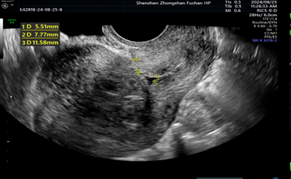

超声报告上写得明明白白:粘膜下子宫肌瘤,足足5cm大!

宫腔镜探头轻轻进入,那颗捣乱的肌瘤原形毕露——个头不小,像个饱满的“山竹”,大半个身子都“赖”在宫腔里。